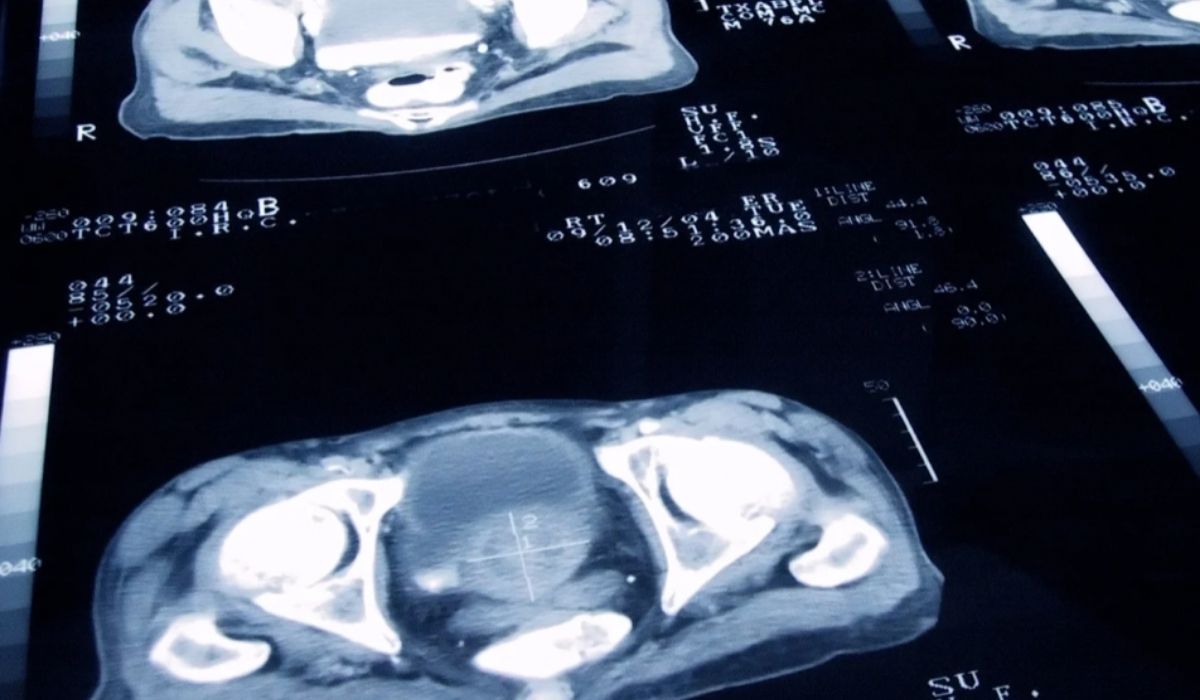

- Badanie fazy III objęło 696 pacjentów z 32 krajów, średnio 68-letnich, z przerzutami raka prostaty.